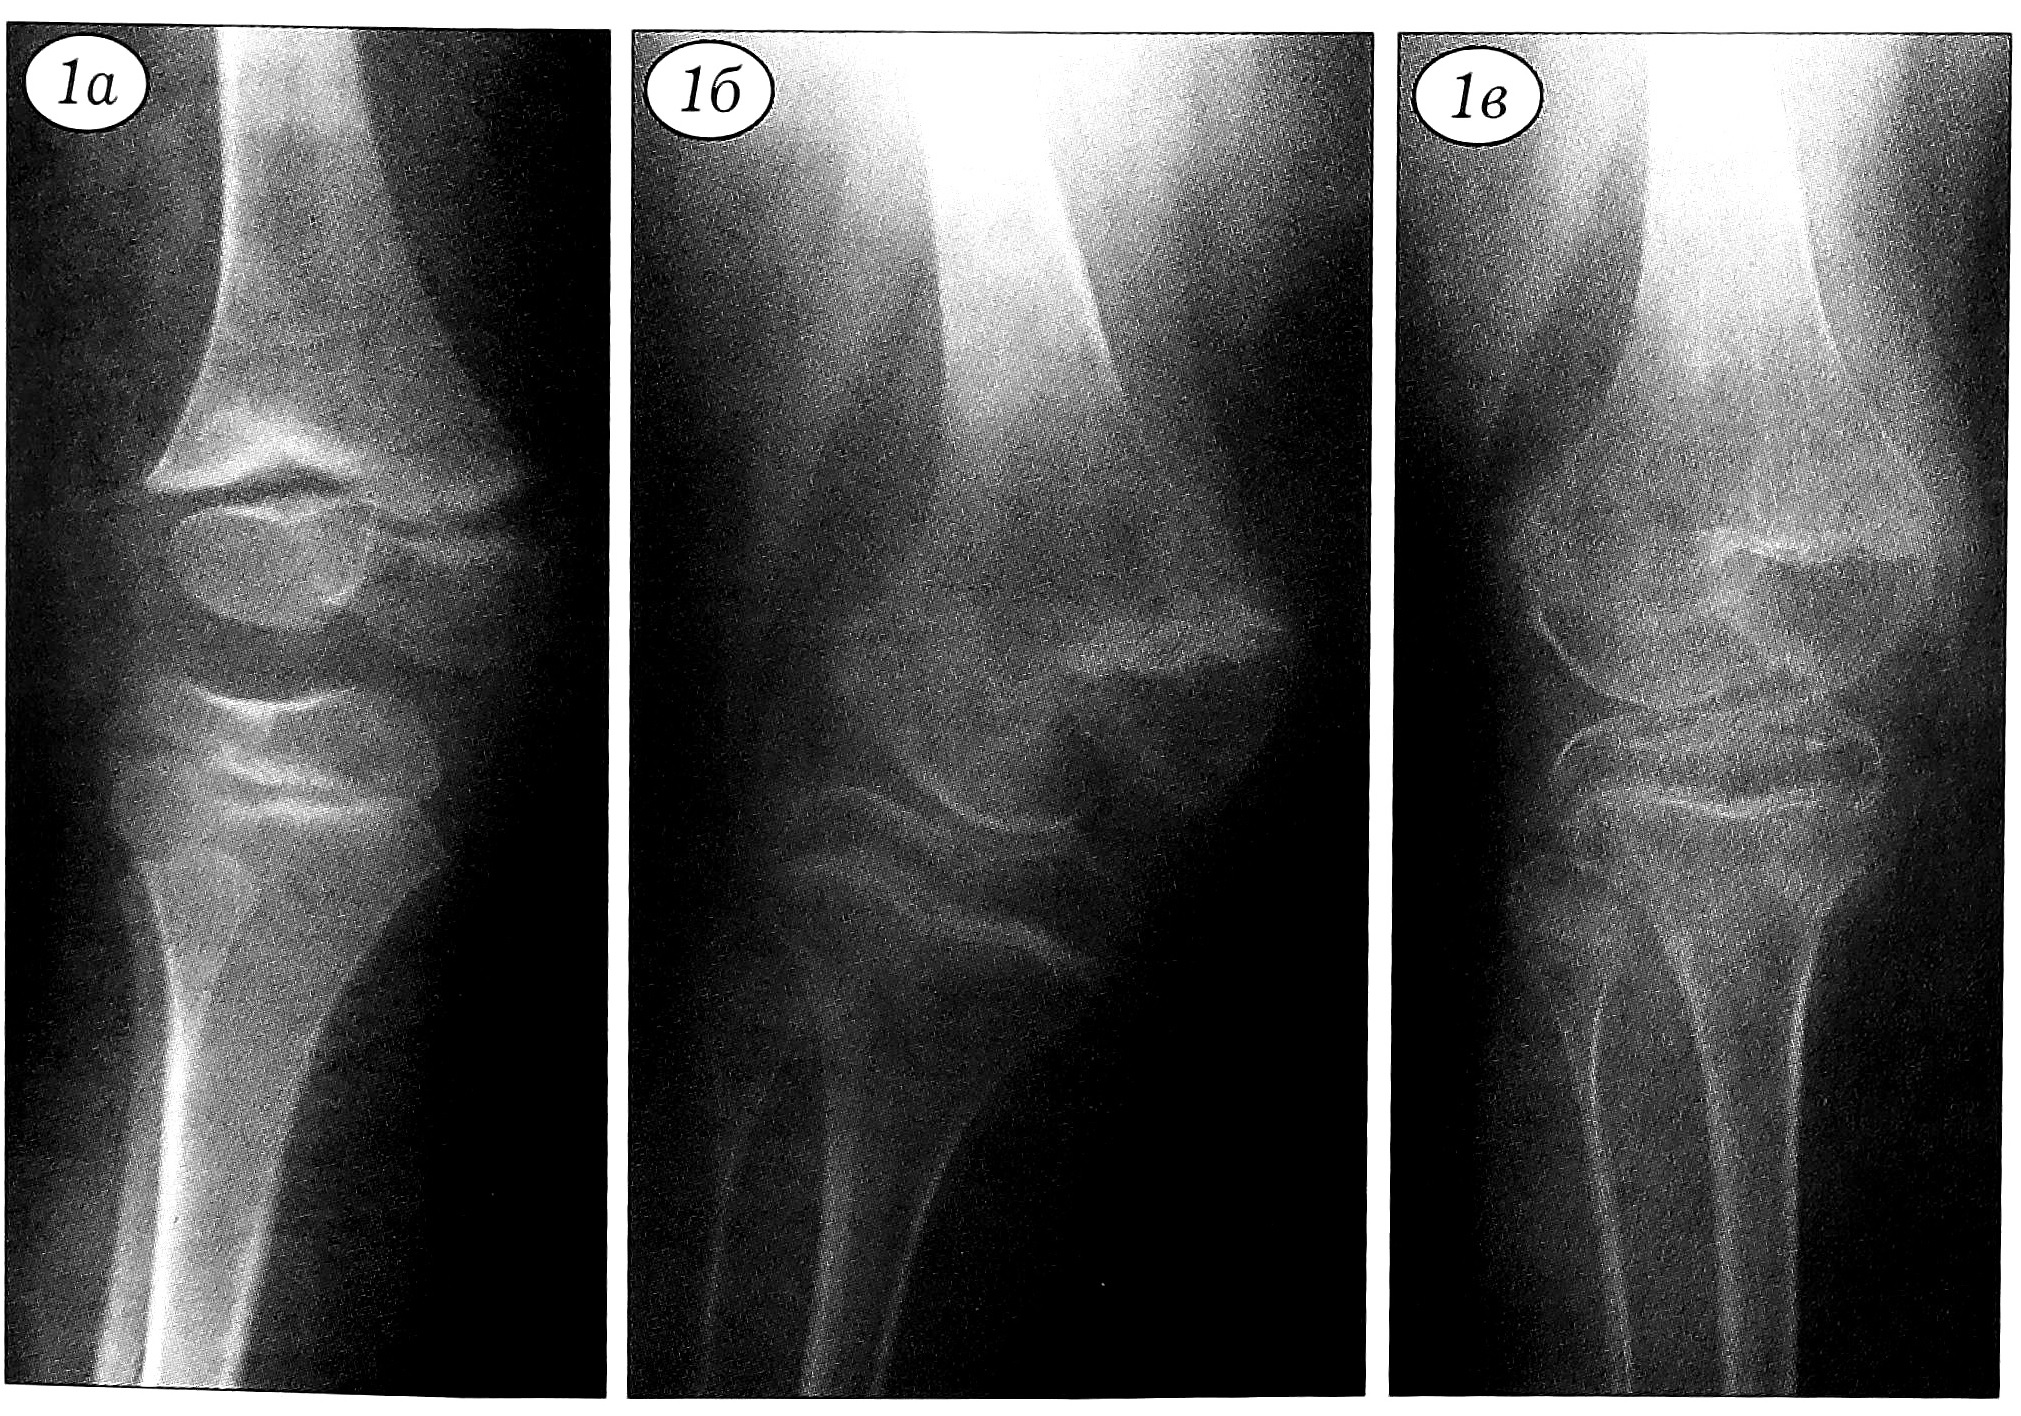

Особенно важным является вопрос о допустимости при системных заболеваниях опорно-двигательного аппарата попыток исправить деформации путем редрессаций, одномоментно вправить вывихи, в том числе и с использованием общей анестезии. Еще в 1949 г. Т.С. Зацепин [12] предупреждал, что при этом надо быть крайне осторожным, так как вместо исправления деформации легко получить перелом. Имеются сообщения о подобных осложнениях при лечении контрактур коленного сустава [31]. Отмечается, что этапные гипсовые повязки и редрессации при остеохондродисплазиях приводят к усугублению контрактур и развитию тугоподвижности в суставах [10]. В то же время ряд авторов [4—6] рекомендуют при неэффективности лечения вывихов в коленном суставе на специальной шине у больных с синдромом Ларсен производить одномоментное закрытое вправление под общей анестезией. Наши собственные данные, а также анализ осложнений, полученных при выполнении редрессаций и закрытых вправлений в других учреждениях, свидетельствуют о крайней опасности использования этих методик. На фоне резкого остеопороза переломы, эпифизеолизы и остеоэпифизеолизы возникают у больных с системными заболеваниями даже при незначительных усилиях, и получить эти осложнения гораздо более вероятно, чем исправить деформацию. Даже в ходе оперативных вмешательств при недостаточном артролизе коленного сустава попытка устранить вывих в нем приводит к сминанию эпифизов. Соответственно, вправление приходится прекращать и производить дополнительное рассечение напряженных сухожильно-фасциальных образований. Практически у всех больных, которым до поступления в институт выполнялись редрессации суставов и предпринимались попытки закрытого вправления вывихов, имелись вторичные деформации эпифизов, в трех случаях отмечалось повреждение зон роста с последующим их асимметричным закрытием, а у одного ребенка — асептический некроз эпифизов костей, образующих коленные суставы (рис. 2).

Рис. 2. Рентгенограмма нижней конечности больного Ш. 2,5 лет. Диагноз: синдром Ларсен. Осложнение после закрытого вправления вывиха коленного сустава (асептический некроз передненаружного отдела эпифиза большеберцовой кости, повреждение проксимальной зоны роста большеберцовой кости, деформация большеберцовой кости после закрытого ее перелома, повреждение дистальной зоны роста большеберцовой кости, парез мышц голени, укорочение костей голени).